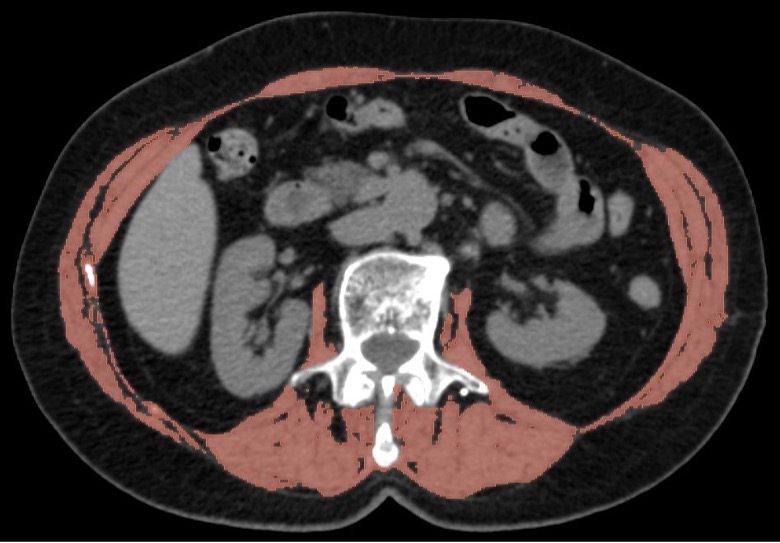

Fig. 1. Preoperative CT scan of a patient without sarcopenia (muscle area 215.5 cm², musculoskeletal index 63 cm²/m²). Muscle tissue is highlighted in red. Axial projection, soft tissue window.

For the purpose of quantitatively evaluating the sarcopenia, we have measured the musculoskeletal index using CT-sarcometry. The measurements were carried out using the axial CT-scans at the level of L3 vertebral bone. The threshold range of the attenuation coefficient varied from -29 to +150 Hounsfield units (HU). A volume of all the skeletal muscles was calculated at the scan zone (paraspinal, major psoas, oblique and rectus abdominal muscles) with excluding other structures. The measurements were carried out by semiautomatic method in the Slicer 5.6.2. software. The segmentation of the image within the pre-set densitometric values was done automatically, while the structures not related to the muscle tissue were removed manually (Fig. 1, 2). The musculoskeletal index was calculated as a ratio of the area of skeletal muscles (cm2) to the square value of the patient height (m2). The threshold values of musculoskeletal index, below which the status of the muscle tissue was considered as sarcopenia, were the classical Prado criteria — 52.4 cm2/m2 for males and 38.5 cm2/м2 for females [15]. For the purpose of simplification of the interpretation of the obtained values, they were presented not as absolute values, but as a ratio of the obtained value to the lower margin of the reference ranges for the given gender (musculoskeletal index). Besides, all the patients at the pre-operative stage had their BMI, body mass and height measured along with the levels of hemoglobin, iron, albumin, transferrin and total protein in blood.